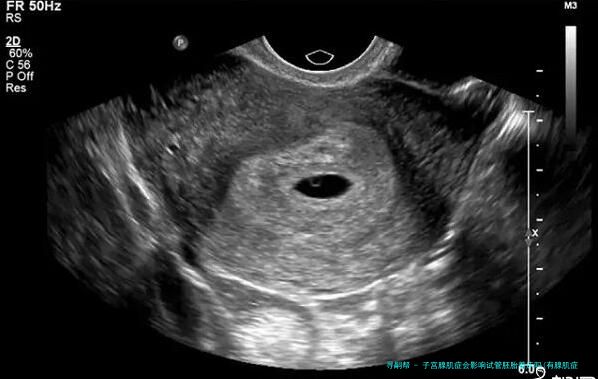

要知道,有很多性友人都患有子宫腺肌病,因此生育受阻。此外他们在长远治疗后择了试管来辅助怀孕,这也正是他们问第一个问题的缘故。如此到底什么是子宫腺肌病呢?据这个专业人士讲解,子宫腺肌病是一种多见的妇科疾病,主要是缘由是子宫内膜腺器官和间质侵入子宫肌层,造成弥漫性或局限性病变。患病人群多为30-五十岁的经产妇(即生过1个以上孩子的性),但年少的没有子女性也有机会患病。

子宫腺肌病会导致试管婴儿的成功率下降,因为在子宫腺肌病的影响下,子宫内膜会移位,引发炎症反应,子宫变大,强化了子宫的收缩功能,因而会影响胚胎的着床。很多条件下,即使胚胎植入成功,后期流产率也会高于正常人。因而想做试管婴儿的性朋友可以先做相关治疗,再做试管婴儿,以免影响试管婴儿的成功率。

子宫腺肌病一朝产生,可能会出现月经错乱、痛经等症状。这主要是因为子宫腺器官和间质侵入子宫肌层形成弥漫性或限制性病变,导致全子宫血液流动不畅,即供血不足,使子宫内膜容受性变差,从而影响胚泡的顺当着床或早产(普通子宫腺肌病多发生于30~50岁左右的产后一个月妇,但也多见于年轻未育妇或妊娠次数过多,容易发生,另有)

子宫腺肌病可以表现为1个坚硬的结节。子宫腺肌病较重的情况会像个球,导致子宫增大,质地松垮,活动本领差。统计表现,百分之十五~40%的子宫腺肌病会并发子宫内膜异位症,约对折患者会并发子宫肌瘤。因此要是不经处置直接移植胚胎,会影响胚胎的着床,降低性的怀孕率。因而关于患了子宫腺肌病的性,建议先进行试管婴儿的诊断和治疗,痊愈后再进行移植,如此成功率更高,好孕率更有保证。大家周知,子宫内膜是胚胎最终着床发生育之处,是保证着床成功率的基础。而且子宫腺肌病会直接影响子宫内膜的质量和宫内环境,所以自然会妨碍胚胎着床。